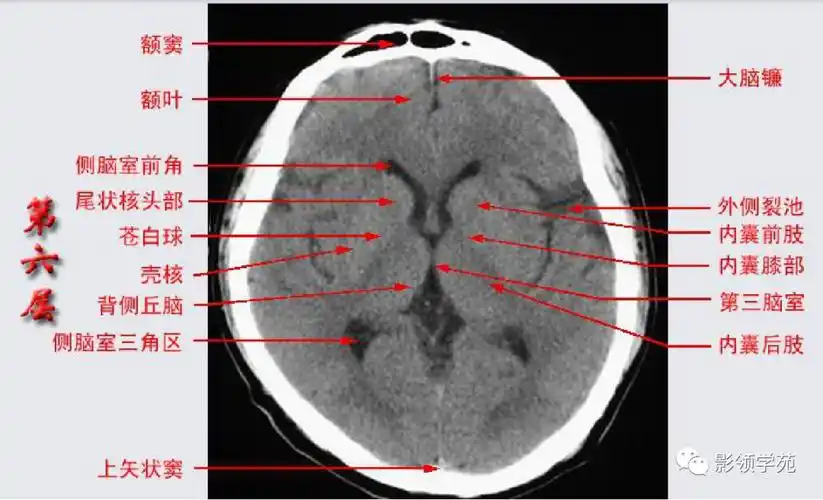

简明又详细的头部ct读片详解收藏

收藏!影像医生必备 | 手把手教你读懂颅脑ct

头部ct影像解剖